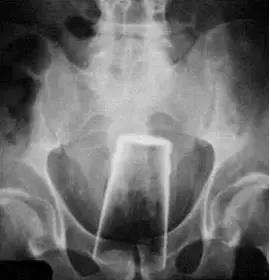

1、可能拿不出来。因为阴道情况复杂,并不是大家所想象的放进去取出来就好了。一旦取不出来,不要强行往外拽。立即前往医院取出。医生一般会先尝试顺滑油,实在不行就只能经手术取出了。